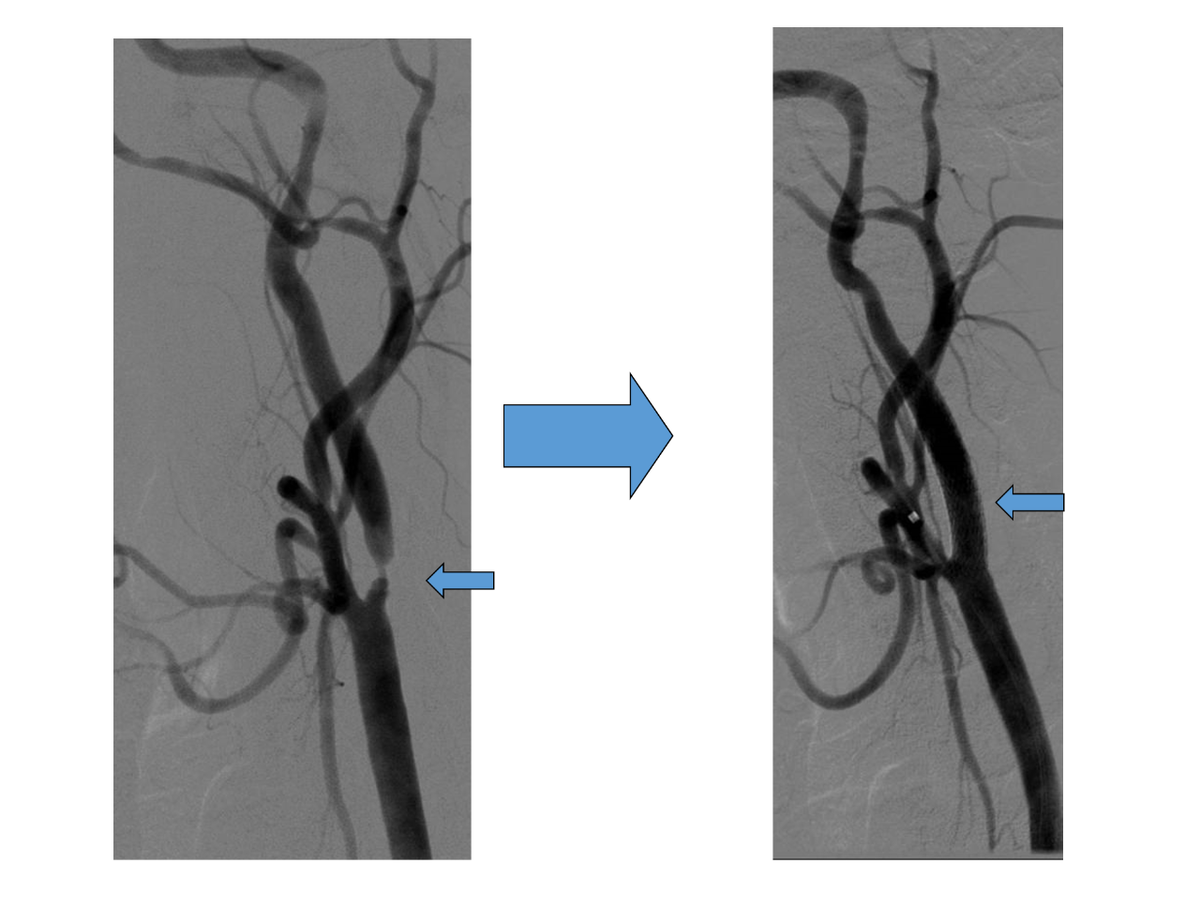

• Катетер проводят к сонной артерии под контролем рентгеновского излучения.

• Вводят контрастное вещество, чтобы увидеть артерию на экране.

• За место сужения хирург проводит устройство для предовращения миграции компонентов бляшки в сосуды головного мозга (церебральная протекция).

• Хирург устанавливает стент, который расширяет суженный участок.